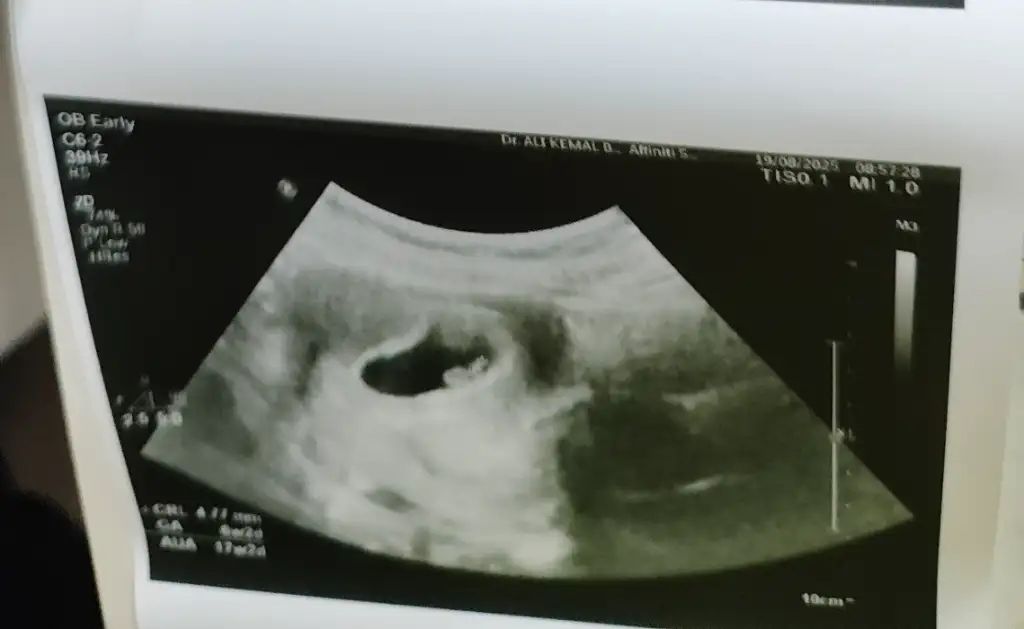

Bende 6+3 te gitmiştim fasulye şeklindeydifasulye ise erkek yuvarlak ise kız diyorlar bir inanışa göre

Vallahi keseyi bende öyle görünce bir tuhaf oldum. Değişik hissettim. Hatta oğlumda geldi o da gördü. Diyor ki baba ben annemi doktora getirdim.. Çok duygusal geçti. .Ya bildiğin kalp şeklinde maşallaherkek kesesi düzgün olmaz kız kesesi daha düzgün olur derler hep o yüzden dedim

Bakalım doğru çıkacak mı. O halde Benimkide erkek mii. Yeniden erkek annesi mi olacağım.6+3 teki görüntü buydu gören hep erkek dedi

Bende instagram da gördüm hep bu sekile erkek diyordular nedense hepde doğru çıkıyordu6+3 teki görüntü buydu gören hep erkek dedi

Aaa evet benim de gördüğüm yorumlarda hep uzun fasülye şeklindeyse erkek yuvarlak ovalar kız diyorlardı. Sizinki bildiğiniz fasülye sanki oğlannnn6+3 teki görüntü buydu gören hep erkek dedi